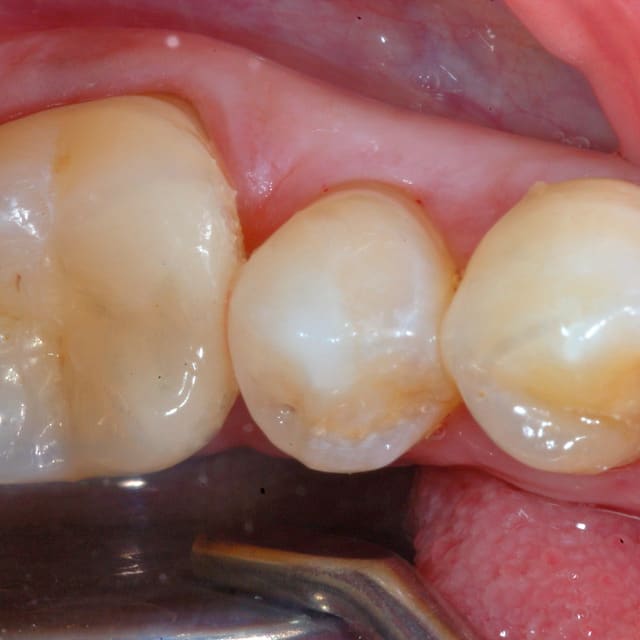

Oui le compo à été fait le jour du collage, en fait l'amalgame me semblait bien mais aprés dépose de celui sur la 6, j'avais un doute sur une infiltration mésial, j'ai donc déposé le plombage sur 7 le jour de la pose de l'onlay

J'ai monté mon compo en me servant de l'onlay pour modeler la face mésial du composite, puis j'ai collé l'onlay dans un second temps...

Un petit cas avec remontée de marche,collé au secure!